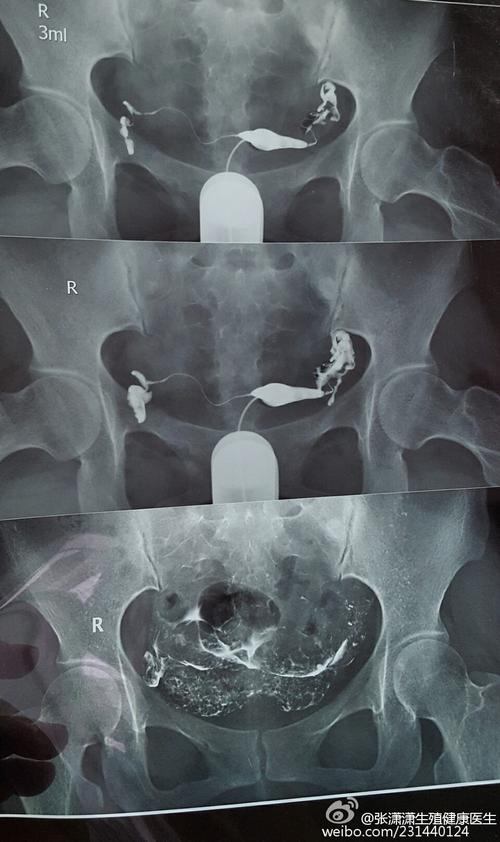

2.在输卵管造影的检查时候,输卵管造影是需要使用X射线来对女性输卵管造影的部位部位进行测序的,这个部位需要在宫腔镜里面去触诊,而且需要在阴道镜里面去触碰,观察输卵管造影的情况,不过,这个是不用检查的。